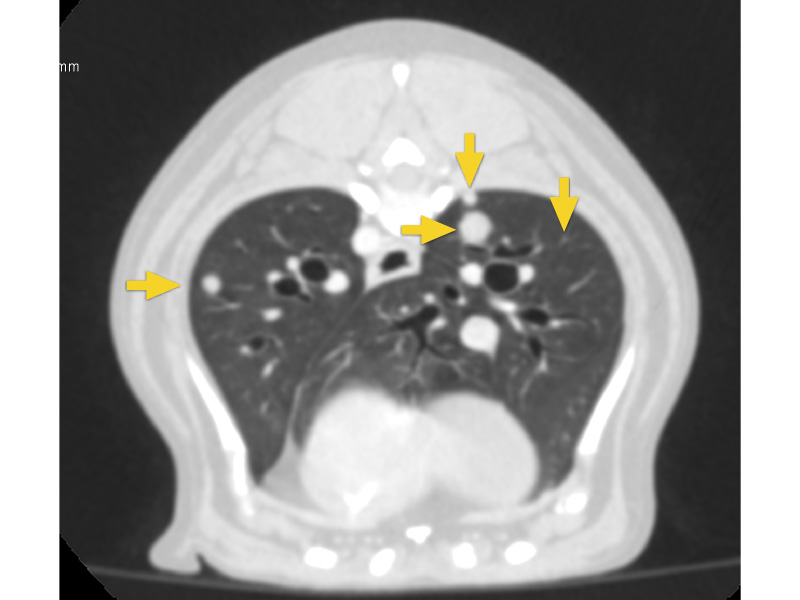

CT検査例① がん肺転移の検出

腫瘍診療では肺転移があるかどうかを調べることが重要です。レントゲンでは見つからない微小な転移病変もCTでは見つけることができます。

CTでは肺全域に最大7mm程度の転移病変(黄色矢印)が確認できますが、この時点でのレントゲンでは見つけられませんでした。